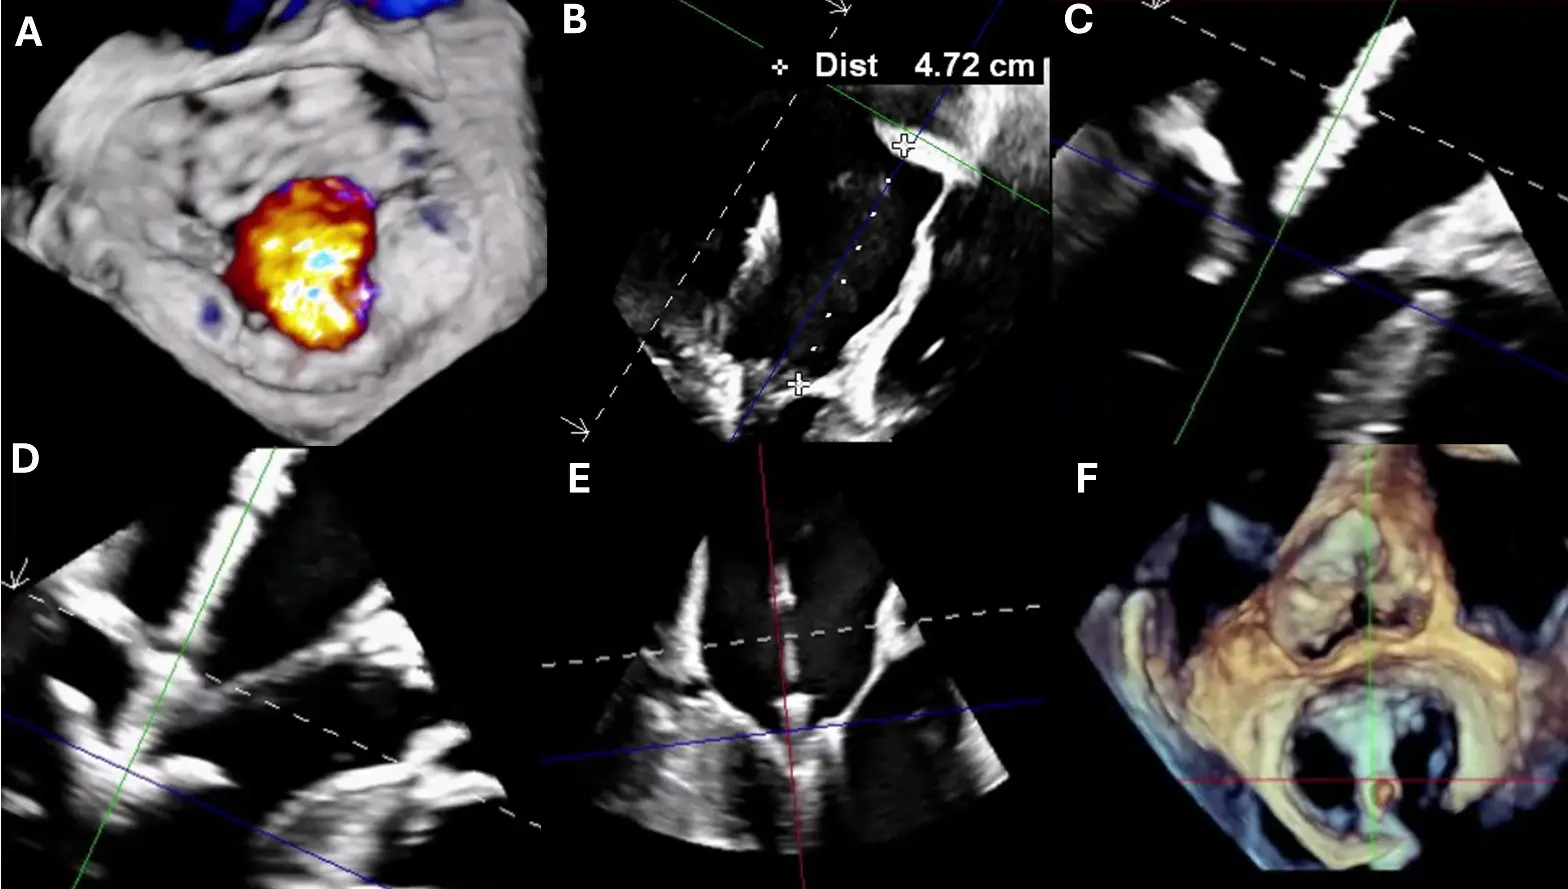

Finally, specialized echocardiographic studies are used in specific clinical scenarios [44,63,83,84]. Stress echocardiography, preferably with exercise, is recommended when the severity of MR at rest does not correlate with clinical symptoms [40,63,85]. Key findings associated with adverse outcomes include a dynamic increase in MR severity (e.g., an EROA increase ≥13 mm2) or the development of pulmonary hypertension (PASP ≥ 60 mmHg) [40]. Transesophageal echocardiography (TEE) is essential when transthoracic echocardiography images are inconclusive and is mandatory for procedural planning and guidance [2,86]. TEE provides superior, high-resolution visualization of leaflet morphology, coaptation depth, and annular geometry (Figure 5) [2,86]. 3D TEE, in particular, offers a “surgical view” that is critical for assessing suitability for TEER and other transcatheter interventions [63,83,87]. During the MitraClip procedure, TEE is used for device navigation, guidance of transseptal puncture (e.g., measuring height from the annular plane), precise leaflet grasping, and assessment of the final post-deployment result [63,86]. This step-by-step guidance is critically important, as demonstrated in Figure 2.

Figure 5. Transesophageal Echocardiographic Guidance During MitraClip Procedure for Severe Mitral Regurgitation. (A) Three-dimensional multiplanar reconstruction (MPR) of the mitral valve from the left atrial (surgeon’s) view demonstrating severe mitral regurgitation (aliasing/mosaic pattern consistent with high-velocity regurgitant flow). (B) Bi-caval TEE view showing successful transseptal puncture with a posterior and superior approach; height from the mitral annular plane measured at >4 cm, appropriate for clip delivery. (C) TEE long-axis view illustrating the MitraClip device crossing the mitral valve into the left ventricle. (D) Device arms fully opened within the left ventricle prior to leaflet capture. (E) Leaflet grasping with approximation of the anterior and posterior leaflets under real-time TEE guidance. (F) Final post-deployment result with stable clip position. Colored lines denote orthogonal 3D multiplanar reconstruction reference planes; white ‘+’ markers indicate caliper/cursor points; the ‘Dist’ line reports the measured transseptal height; dashed white lines outline the imaging sector/3D cropping or MPR slice limits; color Doppler shows the MR jet.